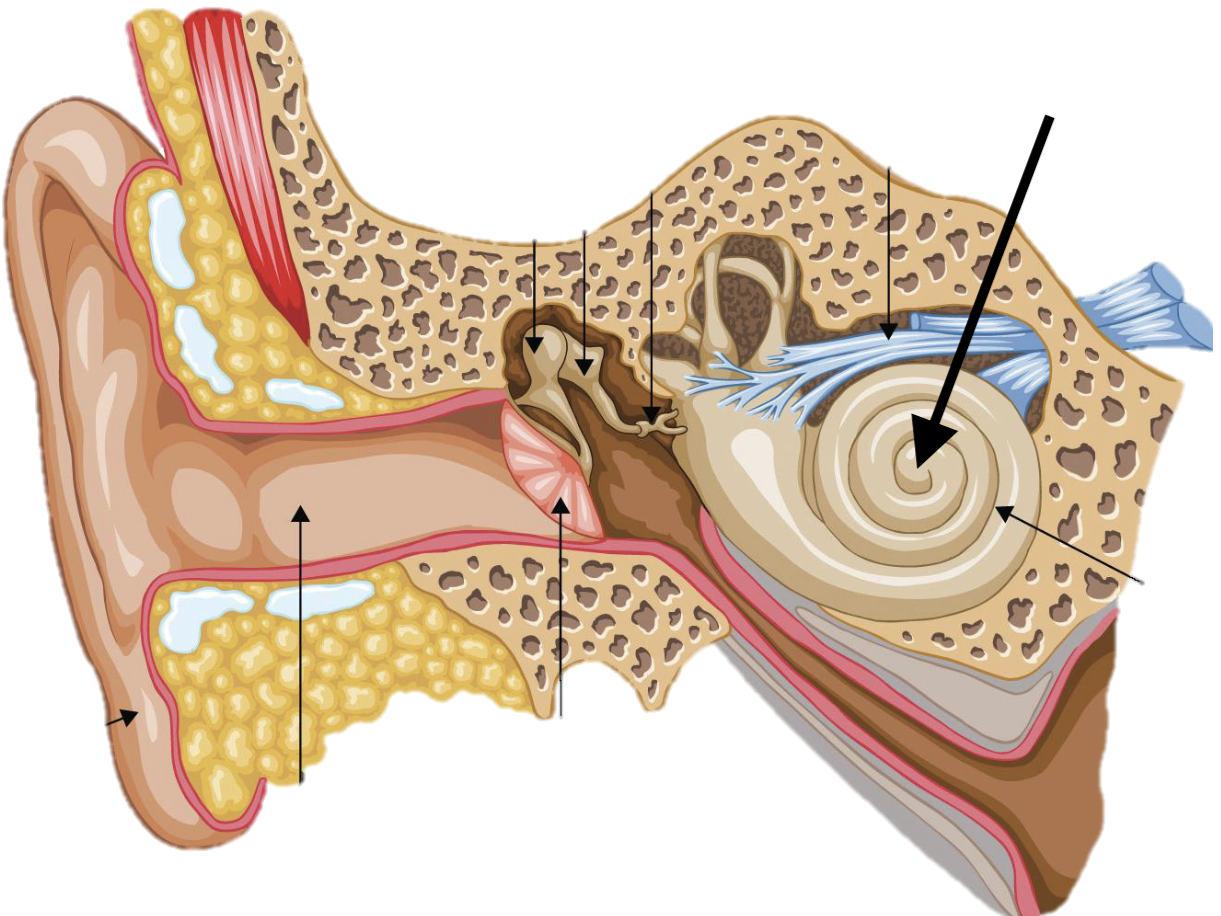

Name the feature of the ear ossicle

External acoustic meatus

Name the feature of the ear ossicle

Malleus

Name the feature of the ear ossicle

Incus

Name the feature of the ear ossicle

Stapes

Name the feature of the ear ossicle

Internal acoustic meatus

Name the feature of the ear ossicle

Cochlea

Name the feature of the ear ossicle

Temporal bone